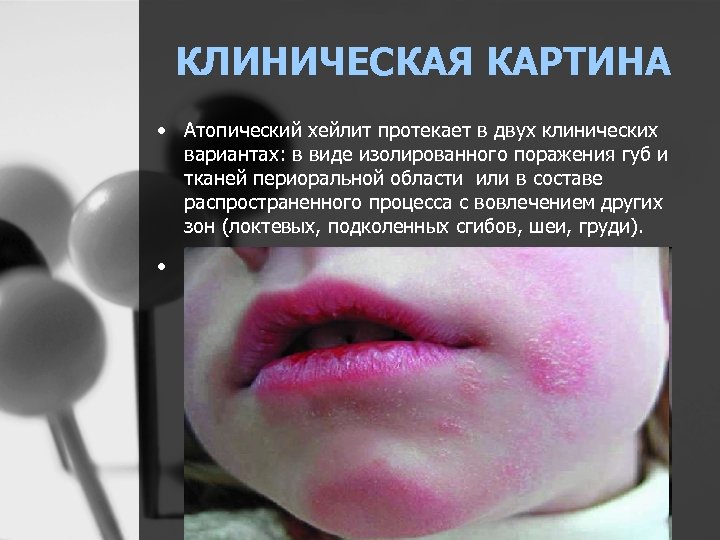

КЛИНИЧЕСКАЯ КАРТИНА • Атопический хейлит протекает в двух клинических вариантах: в виде изолированного поражения губ и тканей периоральной области или в составе распространенного процесса с вовлечением других зон (локтевых, подколенных сгибов, шеи, груди). •

КЛИНИЧЕСКАЯ КАРТИНА • При обеих формах хейлита наблюдают гиперемию и отечность губ, трещины, мелкопластинчатое или крупнопластинчатое шелушение в области наружной части красной каймы губ и в углах рта, инфильтрацию и лихенификацию кожи углов рта, иногда явления периорального дерматита. При изолированном атопическом хейлите чаще определяют мелкопластинчатое шелушение на коже и красной кайме губ и эксфолиативные чешуйки в зоне смыкания губ, а при атопическом хейлите на фоне атопического дерматита обнаруживают более выраженную инфильтрацию губ, отечность красной каймы и слизистой оболочки, отсутствие четкой границы красной каймы и кожи.